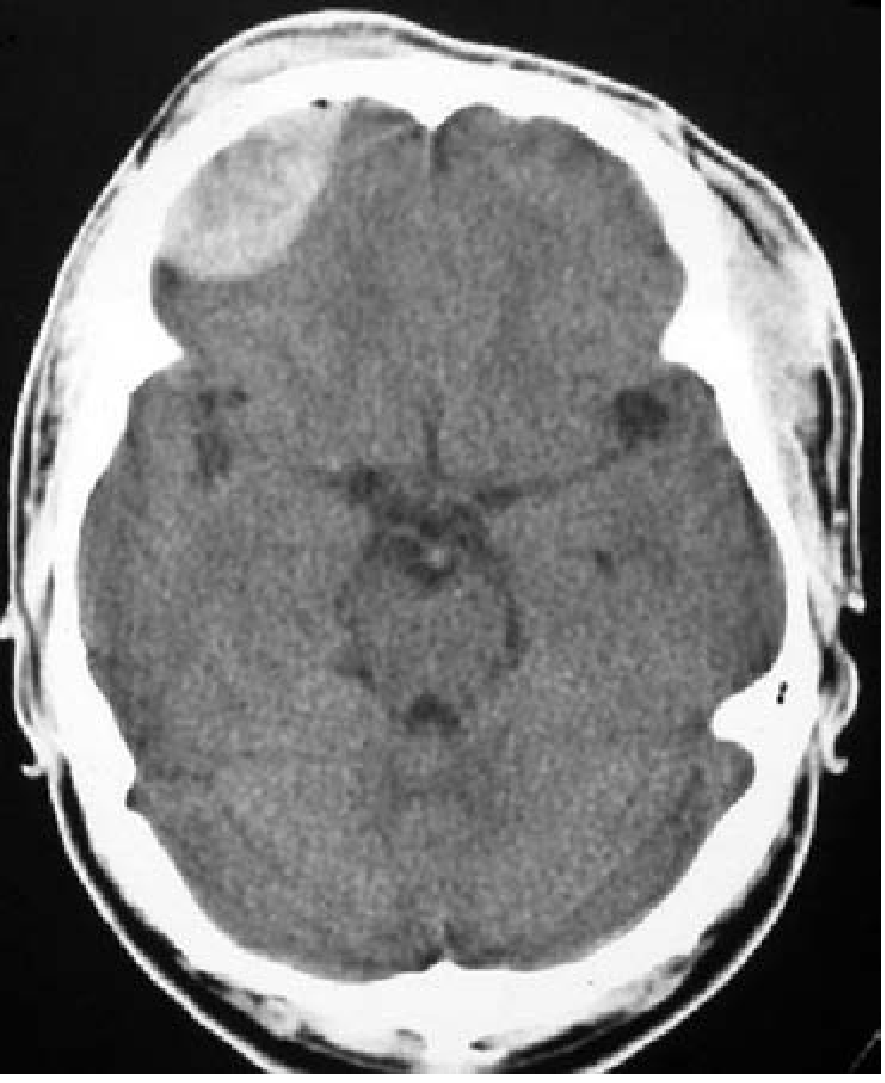

EDH — Biconvex (lenticular/football) hyperdense lesion

EDH CT — biconvex hyperdense collection in right hemisphere

CT scan demonstrating epidural hematoma — note the convex shape and focal location. (Tintinalli's Emergency Medicine)

• Shape: Biconvex (lenticular, football-shaped) — bounded by dural attachments at sutures, cannot cross suture lines

• Location: Most commonly temporal region

• Density: Hyperdense (white) acutely — uniform

• Mass effect: Midline shift, brain compression

• Does NOT cross suture lines